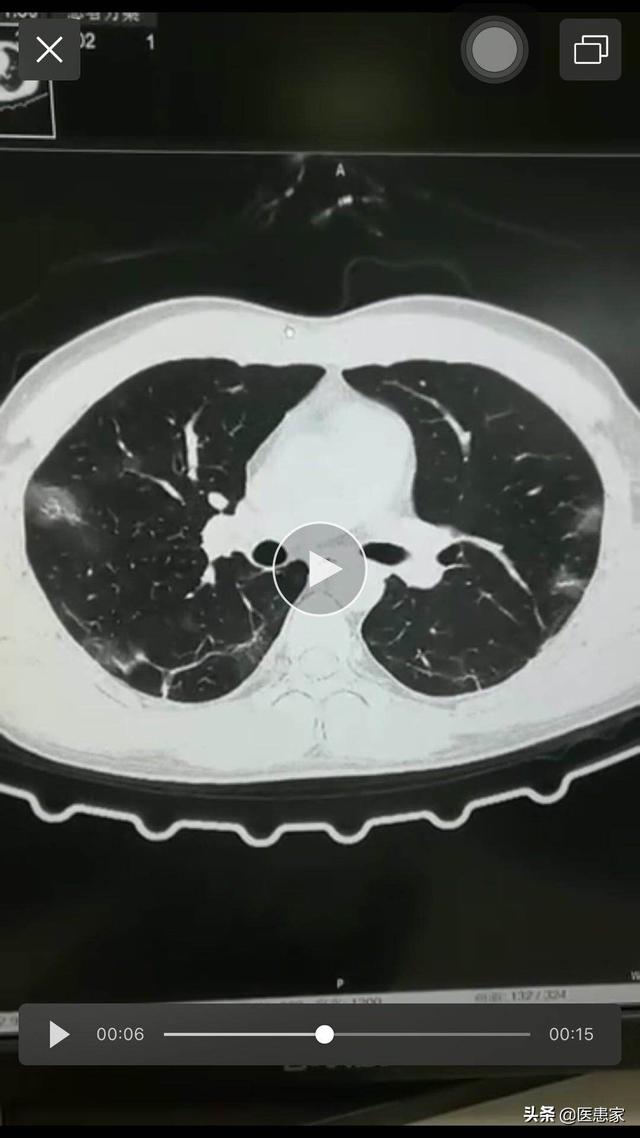

新冠肺炎の重症度は、患者の肺感染症によって異なる。 新冠肺炎が形成された場合、患者は、適切な同定と的を絞った対症療法を行うために、乾いた咳、発熱、倦怠感、より激しい咳、通常は痰のない咳の存在に関心を持つ。

多くの呼吸器感染症と同様に、新生児球菌性肺炎は感染者によって大きく異なる。患者の大半は重篤な肺炎症状を伴い、重症例では呼吸窮迫症候群や呼吸不全に進行するが、心血管系などウイルスが引き起こす他の多臓器障害も死に至る可能性がある。多くの若く健康な患者では病気の経過が予測できず、突然「サイトカインストーム」が起こり、患者の全身を致死的に攻撃する可能性がある。流行の初期には、新型コロナウイルスは小児には感染しない、特定の人種には感染しないという噂が流行の過程で払拭され、ウイルスの前では、人間が感染する可能性は「万人に平等」と言える!ウイルスの前では、人間が感染する可能性は "万人に平等 "と言える。

現在、新型コロナウイルスの特徴や病原性はまだ解明されておらず、各国の科学者が綿密な研究を行っている。世界的大流行の現状から見ると、新型コロナウイルスとSARS、インフルエンザなどのウイルスは大きく異なり、寒冷地と熱帯の国々で流行が発生する可能性がある。無症状の感染者が存在し、他の人に感染した無症状の感染者、潜伏期間が極めて長い患者などが出現する。基礎疾患がなく、若者や高齢者の患者が死亡するケースが出現する。病気の経過が長いため、重症化し、医療システム全体に影響を与える医療スクイーズが出現する可能性がある。新型コロナウイルスに対する私たちの理解は、当初は十分な注意を払っていなかったこと、その重大性を発見したが死亡は高齢者や基礎疾患のある患者に集中していると考えていたこと、多臓器不全を引き起こす可能性があること、軽症の患者や若年成人が突然の不全で死亡する可能性があることを発見したこと、そして新型コロナウイルスの病原性、有害性、重大性も治療の過程で常に更新されてきたこと、から発展してきた。